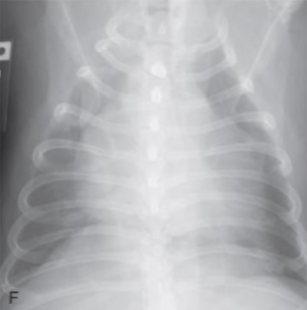

| VHS | Vertebral heart score.![]() | ์ฌ์ฅ ํฌ๊ธฐ์ ์ฒ์ถ๋ผ์ ๋น๊ต. - ์ฅ์ถ : carina์ ventral border์์ ์ฌ์ฅ์ apex๊น์ง (fat ํฌํจํ๋ฉด ์ ๋จ) - ๋จ์ถ : ์ฅ์ถ๊ณผ ์์งํ๊ฒ, CVC ๊ทผ์ฒ์์ ๊ฐ์ฅ ๋์ ๋ฒ์ โ T4 ๋งจ ์์ชฝ๋ถํฐ ์ฅ์ถ/๋จ์ถ ๊ธธ์ด๋งํผ ๊ฐ์ ๋ ์ฒ์ถ๋ผ์ ๊ฐ์๋ฅผ ๋ํจ. Dog : 8.5 Cat : 6.7 |